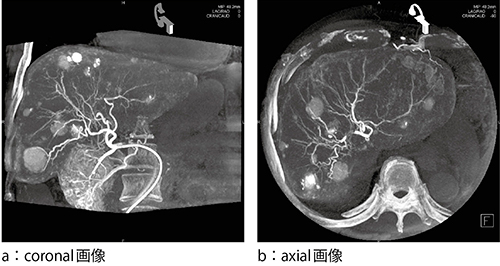

■syngo DynaCT

シーメンスは,2004年にCアームによるコーンビームCT“syngo DynaCT(DynaCT)”を発表し,広いダイナミックレンジを有するFPD(平面検出器)と多彩なCT補正アルゴリズム,Cアームによるコーンビーム再構成技術を用い,肝実質のような軟部組織を高いコントラスト分解能で描出・表現することを可能とした(図1)。

図1 DynaCT画像